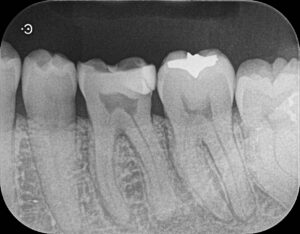

治療後は仮歯を使用してもらい3か月後にレントゲン検査を行い回復傾向にあれば最終補綴物をしていく流れとなります(その歯だけの治療であれば)